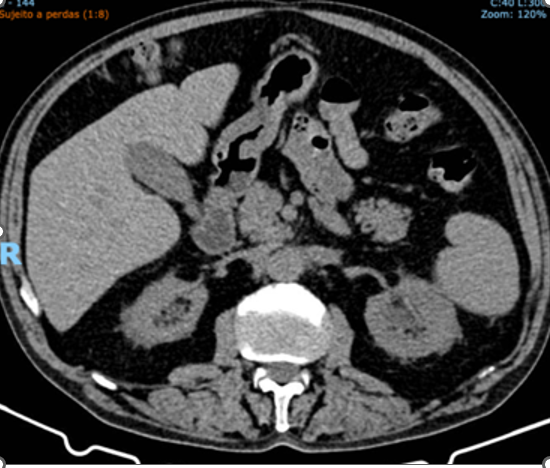

After discharge from our institution, the patient was referred to another hospital with specialties in oncology/hematology, rheumatology and nephrology. He continues to undergo outpatient hemodialysis three times a week and has been maintained on prednisone 20 mg/day for over one year, with significant reduction of retroperitoneal fibrosis (Figures 2 (before)  and  Figure 3 (after)

Figure 3. Total abdominal computed tomography: Image obtained after initiation of corticosteroid therapy, showing improvement of hydronephrosis and significant reduction in the size of the retroperitoneal mass.